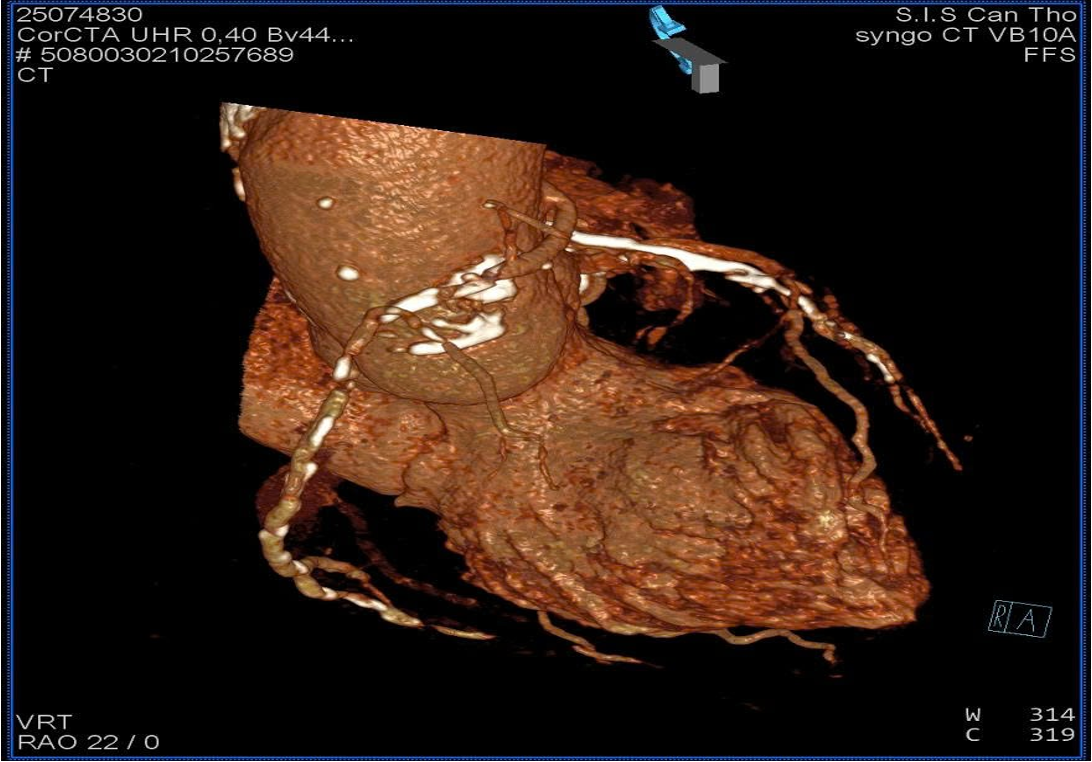

hs-TnI was 6.0 -> 86.6 pg/mL; NT-proBNP of 387.2 pg/mL. Echocardiogram showed hypokinesis of the lateral wall, left ventricular ejection fraction of 52%. No thrombus in the heart chambers, no pericardial effusion. Coronary CT angiography revealed an anomalous RCA origin arising 2 mm above the left coronary sinus from the aorta. CT-based reconstruction identified the optimal orthogonal viewing angle for the RCA ostium as RAO 22 ¡Æ.

Coronary angiography of the RCA was initially attempted using a Tiger 3.5 5 F and a JR 4.0 5 F catheter but proved unsuccessful. A JL 3.5 5 F catheter was subsequently employed to selectively engage the left coronary sinus; however, after 30 minutes, selective cannulation could not be achieved. Guided by CTA findings, a JR 4.0 6 F guiding catheter was advanced, and with the gantry positioned at RAO 22 ¡Æ, successful selective cannulation of the RCA was achieved with ease.